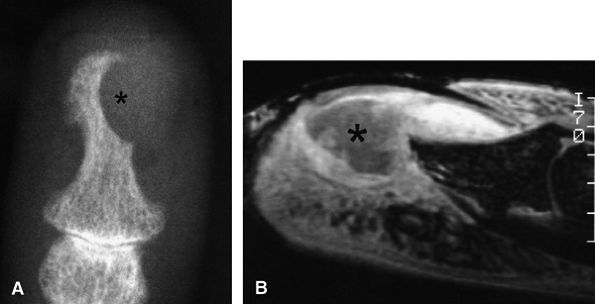

FIGURE 11.73 ● Giant cell tumor of the tendon sheath. Lateral view radiograph shows a large mass of the palmar soft tissue (asterisk) and bone pressure erosion (arrows).

FIGURE 11.74 ● Giant cell tumor of the tendon sheath. Sagittal T2-weighted image (A) and post-contrast T1-weighted image (B) show a palmar mass (arrows) close to the sheath of the flexor tendons with predominant low signal (arrowhead) on the T2-weighted image and strong enhancement following contrast administration.